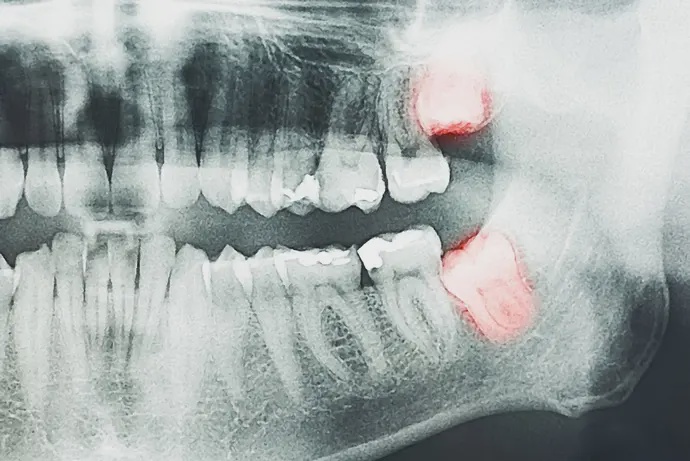

Думаете об удалении зуба мудрости, но боитесь, что потом будет больно? Уже прошли операцию, но болит челюсть после удаления зуба мудрости? В этой статье стоматолог Ковалев Алан Вадимович расскажет, какая боль после удаления восьмерки нормальная, а когда стоит обратиться к врачу. Почему болит после удаления зуба мудрости? Зубы мудрости крупнее других, а также имеют более сложную корневую систему (от 1 до 6 корней). Часто его удаляют по частям. Поэтому это сложная хирургическая операция. При удалении зуба образуется рана, которое заживает около 7 дней. Если после удаления зуба мудрости болит, то это во многом зависит от сложности проведения хирургической операции. Если корни не были сплетены, зуб цел и в ротовой полости не было таких патологий, как периодонтит или пульпит, то риск осложнений минимальный. Если есть искривление, горизонтальное прорезывание, переплетение корней, то экстракция будет более глобальной, а риск осложнений повышается. Есть и другие факторы, которые влияют на боль после операции: Снижение иммунитета. Нарушение техники проведения процедуры. Игнорирование рекомендаций врача, касающихся гигиены полости рта после удаления зуба. Как расположение зуба мудрости может влиять на уровень боли? У нижних зубов мудрости более глубокие корни (расположены ближе к нижнечелюстному нерву). Их удаление часто требует разреза десны или распила зуба (верхние можно удалить только с использованием щипцов). Поэтому боль после удаления нижних восьмерок может быть сильнее и дольше. Почему так больно удалять зубы мудрости? Потому что восьмерки имеют сложную корневую структуру, часто имеют неправильный наклон и могут врастать в соседние зубы. Часто ткани и кость вокруг них очень плотная – требуется глубокое вмешательство. Анестезия не всегда покрывают всю зону. Почему десна болит через 7 дней после удаления зуба мудрости? Потому что могут быть затронуты нервные окончания или долго восстанавливаются поврежденные ткани. Боль более 7 дней может быть признаком инфекции, альвеолита. Рекомендуем обратиться к стоматологу при первых симптомах осложнения. Сколько длится боль после удаления зуба мудрости? При нормальном заживлении тканей и без осложнений боль после удаления зуба мудрости длится 7 дней. После процедуры на месте раны образуется фибрин - сгусток крови, который защищает рану от инфекции и формирует новую ткань. Если осложнений нет, то далее следуют такие этапы залечивания раны: После вмешательства боль начинает проявляться примерно через 3 часа, когда действие анестезии заканчивается. На 3-4 день фибрин начинает преобразовываться в грануляционную ткань. При этом пациент ощущает ноющую боль. На месте вмешательства будет покраснение, возможен отек. На 7 дней боль притупляется, отек проходит. Это свидетельствует о том, что ротовой полости обеспечен нужный уход и проходит заживление. В течение следующих двух недель пациент может наблюдать небольшую болезненность ближе к вечеру. Любой дискомфорт должен пройти через 3 недели. Через 4 недели грануляционная ткань замещается соединительной, которая полностью заполняет лунку. Через 3 месяца на месте удаления образуется костная ткань. Если болевые ощущения не проходят в течение недели, а наоборот боль становится пульсирующей, возникает отек и температура повышается, то срочно нужно идти к врачу. Эти симптомы указывают на осложнения. Боль от осложнений после удаления восьмерки Рассмотрим симптомы, которые могут быть признаками осложнений. 1. Болезненность и кровоточивость десен Основными причинами таких симптомов являются: Травмирование десен во время операции. Процесс восстановления, запущенный организмом, также вызывает болезненные ощущения. Кровоточивость иногда связана с повреждением сосудов в десне. Определенный уровень болезненности является нормальным. Выявить, что кровоточивость и болезненность являются ненормальными, можно по таким признакам: Боль не проходит, становится резкой. Это говорит о том, что в зоне повреждения возникло воспаление. Кровотечение не проходит в течение 48 часов. Это может быть признаком нарушения свертываемости крови, повреждения сосудов и инфекции. 2. Боль в челюсти и ограниченная подвижность Такое может происходить при удалении нижних зубов мудрости, так как они расположены глубоко рядом с крупными жевательными мышцами. Удаление вызывает дополнительную нагрузку на челюсть. Для снятия боли используются противовоспалительные препараты, которые применяются только по назначению врача. Если боль в челюсти и ограничение подвижности сохраняется более 7 дней, то это повод записаться на прием в нашу клинику. 3. Боль в месте удаления Если боль усиливается через неделю после операции, становится пульсирующей, то это может указывать на наличие инфекции. Признаком осложнения при боли в месте удаления может быть резко усиленная, пульсирующая боль. Она может сопровождаться покраснением, отеком. Это является признаком инфекции или развития альвеолита. 4. Боль в соседних зубах Причиной дискомфорта в соседних зубах бывают: Если зуб мудрости был вросшим или находился близко к другим зубам, то во время операции могло возникнуть давление на них. Отек и воспаление в области удаления может распространяться на соседние зубы. Были микротравмы десен во время манипуляций. Это влияет на болезненность зубов, расположенных в зоне травмирования. Жевательная нагрузка изменилась после удаления зуба, что также может вызвать временную болезненность. Затронуты нервы, передающие ощущения в соседние зубы. Наличие инфекции или “сухой” лунки. 5. Боль в ухе Причиной такой боли чаще всего являются нервные импульсы, которые передаются от нижних зубов, расположенных близко к нервам. Такое явление называется иррадиацией боли. Боль в ухе иногда связана с травмой или воспалением. Обратитесь к стоматологу для диагностики, если боль в ухе не проходит более 4 дней и при этом сопровождается отеком и покраснением. 6. Боль в горле и при глотании Часто это связано с отеком или воспалением, которые распространяются и на горло. Для уменьшения боли нужно пить много теплой жидкости, избегать острой пищи и полоскать рот солевым раствором. При усилении боли нужно обратиться к врачу, который исключит инфекцию. 7. Пульсирующая боль Причинами пульсирующей боли может быть инфекция, “сухая лунка”, а также повреждение нервов и перенапряжение тканей. Если пульсация не проходит или усиливается, то стоит записаться к стоматологу. Что усиливает боль после удаления зуба? Усиление боли связано с такими факторами: Сложность операции. Воспаление лунки. Наличие в лунке костного отломка. Повреждение кровеносных сосудов или нервов. При ухудшении самочувствия, появлению налета, гноя, неприятного запаха, увеличении лимфоузлов обязательно нужно показаться доктору. Как облегчить боль после удаления? Можно облегчить боль такими домашними средствами: В первые 48 часов использовать холодные компрессы. Через двое суток компрессы должны быть теплыми. После появления сгустка крови на месте удаленного зуба рекомендуется промывать его соленой водой. Для облегчения боли можно использовать обезболивающие препараты, которые уменьшают воспаление. Принимать их следует только после консультации с лечащим врачом. В период восстановления важно организовать себе больше отдыха, уменьшить физическую нагрузку, особенно первые два дня после операции. В качестве продуктов стоит выбирать жидкую и мягкую пищу в виде супов, соков, пюре, смузи, йогуртов. На период реабилитации лучше отказаться от острой еды, которая вызывает дискомфорт в ротовой полости. Если после удаления зуба мудрости болит нижняя челюсть и воспаление не проходит больше недели, то это может быть причиной инфекции. В таком случае нельзя тянуть с посещением врача. Вопросы-ответы Нормально ли, что после удаления зуба у меня повышается температура? Да, повышение температуры является нормальной реакцией организма на хирургическое вмешательство. Но если температура не снижается больше 7 дней, то обязательно нужно идти к врачу. Как избавиться от кариеса самостоятельно? Моя щека опухла. Нормально ли это? Отек щеки является нормальным после получения травмы. В большинстве случаев он проходит в течение 7 дней. Если на 5-ый день пациент замечает увеличение отека, покраснение, выделение гноя, увеличение интенсивности боли, то это является поводом звонить в клинику. Когда можно начинать чистить зубы в области удаления? Чистить зубы после процедуры удаления нужно с осторожностью. В первые 24 часа нельзя ни чистить зубы, ни полоскать рот. Со второго дня можно аккуратно чистить зубы, избегая поврежденной области, чтобы не переместить сгусток. Через 7 дней можно вернуться к нормальной чистке зубов, но к зоне повреждения нужно по-прежнему относиться осторожно. Рекомендуем использовать щетку с мягкой щетиной. Что делать если не могу открыть рот после удаления восьмерки? Это явление, называемое тризм, распространенное. Оно появляется из-за воспаления тканей зуба или жевательных мышц. Для облегчения состояния в нашей клинике мы рекомендуем прикладывать к щеке теплые компрессы на 15 минут в день, делать гимнастику, плавно открывая и закрывая рот, а также соблюдать диету с мягкими продуктами, не требующими жевания (йогурт, пюре, смузи). Если стоматолог прописал противовоспалительные препараты, то можно их принимать. В течение 3-х дней рот должен начать постепенно открываться. Если этого не происходит, а появляется отек, покраснение, то нужно обратиться к врачу. Может ли болеть кость челюсти после удаления восьмерки? Да, это возможно, особенно при проведении сложных операций. Такая боль вызвана травмами кости, воспалением тканей или мышечным напряжением. Причиной боли может стать и инфекция, поэтому если боль не проходит больше недели, то рекомендую записаться на прием в нашу клинику. Как ускорить заживление после удаления зуба мудрости? Чтобы ускорить заживление раны после удаления восьмерки, необходимо строго относиться к указаниям врача в отношении гигиены.